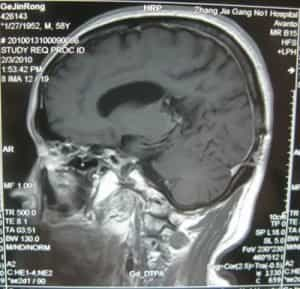

التصوير أثناء الجراحة

فتح الجمجمة عبر المدخل الجداري القذالي الأيسر

فتح الجمجمة عبر المدخل الجداري القذالي الأيسر مع استئصال الورم.